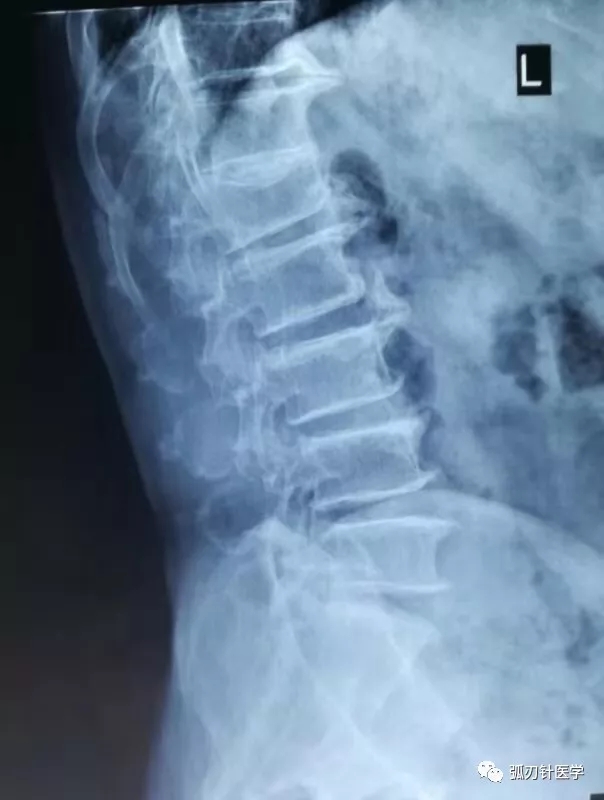

2019年9月底,我第一次接诊73岁的老爷子华某,有肾结石病史的他告诉我:一周前不知道为什么右侧肾区一直沉、痛,医院按肾结石治疗,药吃了好几天也不见轻,这几天更是晚上痛的睡不着觉,听人介绍说我这里治疗疼痛有一套,慕名来诊。 仔细询问病史:老爷子有腰椎间盘突出症,双膝关节骨性炎10余年。年轻时曾有车祸外伤住院史。无过敏史,发病以来,饮食二便可。 辅助检查结果: 泌尿系CT示:左输尿管近膀胱入口处点状高密度影,考虑:结石? 腰椎正侧位:腰椎退行性改变。腰1楔形改变。 腰椎MRI:腰1-骶1椎间盘突出。腰1压缩性骨折(陈旧性) 腰3-骶1椎间盘变性。

基本情况了解后,就需要仔细地查体。老爷子右侧肾区近脊柱旁轻度叩击痛,并可触及广泛条索样、结节样压痛、质硬。随体位改变,呼吸运动,疼痛无变化。墨菲征(-)。腰椎活动度可,两侧腰椎脊突旁、腰3横突压痛,右侧显著。另见胸腰段稍后凸。双侧直腿抬高实验阴性,双侧屈膝屈髋试验弱阳性,双侧“4字”实验弱阳性。 临床上,引起肾区疼痛的原因很多,常见的有以下几种:1、肾脏疾病。如肾或输尿管结石、肾囊肿、肾肿瘤、肾炎等。结石导致的肾区疼痛最为常见,肾结石可有活动后肾区隐痛,如结石掉入输尿管可致剧烈的肾绞痛,结石堵塞输尿管后肾脏积水会产生胀痛。肾囊肿较大、位置特殊(肾盂旁囊肿)或继发感染、出血等,可导致肾区胀痛。肾肿瘤体积较大可刺激肾脏包膜,产生胀痛。肾炎也可致肾区疼痛。2、尿路感染。分为特异性感染如肾结核,及非特异性感染如肾盂肾炎等,均可致肾区疼痛。3、肾虚。肾虚分为肾阳虚、肾阴虚和肾阴阳两虚。肾阳虚是素体阳虚、年高体衰、久病及肾、房劳过度等原因导致的。表现为怕冷、面色偏白、体型偏瘦弱、容易出汗、不耐体力劳动;面部易长斑、咽部常有不适、肩背部不适、易得胃肠病,一吃凉的或吹冷风就腹泻,大便不成形;腰酸、性欲低下、易痛经、月经周期延长。肾阴虚是先天禀赋不足;久病及肾;房事过度,耗精伤阴;过服温燥劫阴之品,耗伤阴液,急性热病后,情志内伤等原因导致的。表现为头晕耳鸣、腰膝酸痛、失眠多梦、潮热盗汗、五心烦躁、咽干颧红、齿松发脱、形体消瘦、小便短黄或大便干结、舌红少津、脉细数,男子兼见阳强易举、遗精、早泄,女子经少或经闭、崩漏等。4、肾上腺疾病。如肾上腺肿瘤或囊肿,体积较大时挤压周围脏器,产生疼痛。5、骨科疾病。腰肌劳损、腰椎间盘突出、腰肌筋膜炎等软组织的损伤,也可导致肾区疼痛。这类患者可能是长期久站久坐、腰部受凉、急慢性劳损等原因导致的软组织损伤。常伴有弯腰时疼痛加重,平卧休息时缓解,偶伴有下肢放射性疼痛麻木,间歇性跛行等坐骨神经痛刺激等症状。综合考虑后,我认为老爷子尽管身上毛病不少,但引起右侧肾区疼痛的原因应该是腰部软组织损伤。这种情况临床上常见,但容易被误诊。找到病因,接下来就是对症治疗。根据王学昌教授提出的“五定原则”,我判定病变组织为腰方肌,依据灶点理论,就在右第12肋骨下缘和腰三横突尖选择灶点,依照弧刃针标准疗法治疗。真的是“四两拨千斤”!别说老爷子本人,就连我也对弧刃针的治疗效果惊叹不已:就1支小针,找准病灶治疗,不到2分钟后,老爷子一脸不可思议的告诉我说不怎么疼了,感觉呼吸通畅了!又过了几天,完全没有不适不适的老爷子满心欢喜地专程前来致谢。